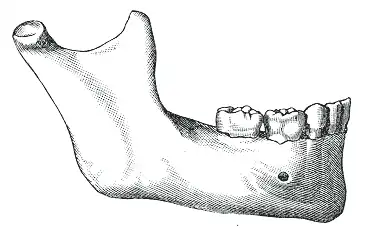

Body

Front view

Left side

The body of the mandible is curved, and the front part gives structure to the chin. It has two surfaces and two borders. From the outside, the mandible is marked in the midline by a faint ridge, indicating the mandibular symphysis, the line of junction of the two halves of the mandible.[6] This ridge divides below and encloses a triangular eminence, the mental protuberance (the chin), the base of which is depressed in the center but raised on both sides to form the mental tubercle. Just above this, on both sides, the mentalis muscles attach to a depression called the incisive foramen.[6] Vertically midway on either side of the body, below the second premolar tooth, is the mental foramen, through which the mental nerve and blood vessels pass.[6] Running backward and upward from each mental tubercle is a faint ridge, the oblique line, which is continuous with the anterior border of the ramus.[6] Attached to this ridge is the masseter muscle (which covers most of the ramus[7] and is a muscle of mastication), the depressor labii inferioris and depressor anguli oris (which support the mouth), and the platysma (extending down over much of the neck).[6]

From the inside, the mandible appears concave. On either side of the lower symphysis is the mental spine (which can be faint or fused into one), to which the genioglossus (the inferior muscle of the tongue) attaches; the geniohyoid muscle attaches to the lower mental spine. Above the mental spine, a median foramen and furrow can line the symphysis. Below the mental spine is an oval depression (the digastric fossa of the mandible) where the digastric muscle attaches.[8] Extending backward and upward on either side from the lower symphysis is a ridge called the mylohyoid line, where the mylohyoid muscle attaches; a small part of the superior pharyngeal constrictor muscle attaches to the posterior ridge, near the alveolar margin. Above the anterior ridge, the sublingual gland rests against a smooth triangular area, and below the posterior ridge, the submandibular gland rests in an oval depression.